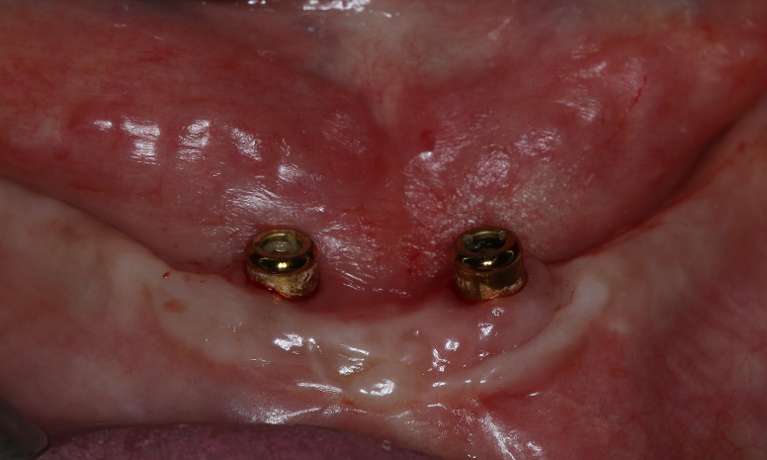

The upper and lower sets of teeth are removed and replaced with removable dentures that are securely held in place by dental implants. This provides improved stability, comfort, and function - leading to a patient who was thrilled with their new smile!

Implant-retained dentures have transformed our patient's smile. This permanent solution provides stability, comfort and a natural look, making it a fantastic option for those missing teeth. Our patient is thrilled with the results - and we are too.

Implant-retained dentures have given this patient a smile that's built to last. This permanent solution not only looks natural but also provides the comfort and security needed to enjoy life to the fullest.